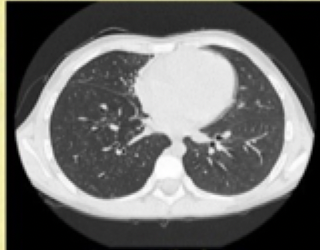

11

Q

what type of window

A

Bone

12

Mediastinal

13

lung

14

What are all the windows

BLM BSA:

mediastinum

brain

soft tissue

abdomen

Windowing = grey-level mapping contrast enhancement

- adjusts the display settings of the CT images to emphasize specific types of tissue, making it easier to diagnose various conditions